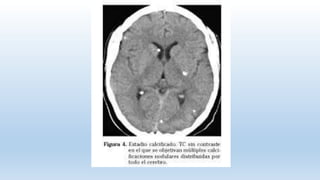

fase de calcificación: incorporación de calcio sobre el tejido fibrótico del

parásito

Fases del quiste. Engeneral, la NCC se presenta como formas intraparenquimatosas, asociadas con cuadros convulsivos, o formas extraparenquimatosas, estando estas últimas asociadas con hipertensión endocraneana. Los quistes intraparenquimatosos pasan por las siguientes fases: fase vesicular: quistes viables, provocan una respuesta inflamatoria mínima. fase coloidal: presencia de inflamación provocada por la respuesta inflamatoria celular alrededor del quiste. fase nódulo granular: sustitución gradual por tejido fibrótico y colapso progresivo de la pared del quiste. fase de calcificación: incorporación de calcio sobre el tejido fibrótico del parásito